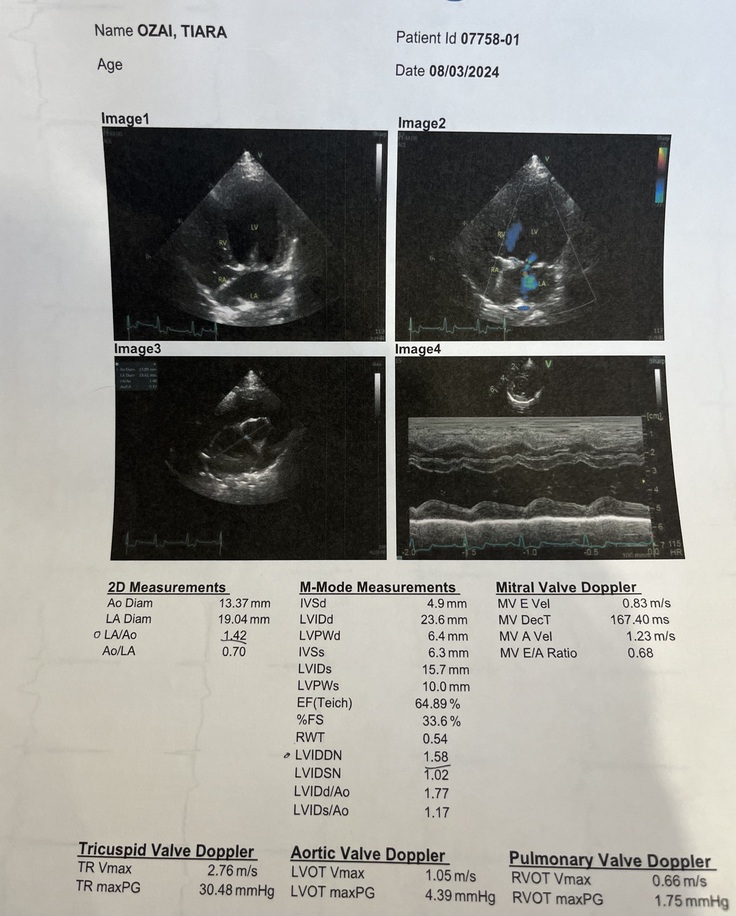

2024.3.10 術後三ヶ月検診のご報告です✨

先日、術後三ヶ月検診に行ってきました。

心臓は順調に回復に向かってくれており

逆流も0ではありませんでしたが

問題ない状態にまで回復する事ができ

心臓も小さくなっておりました🫀